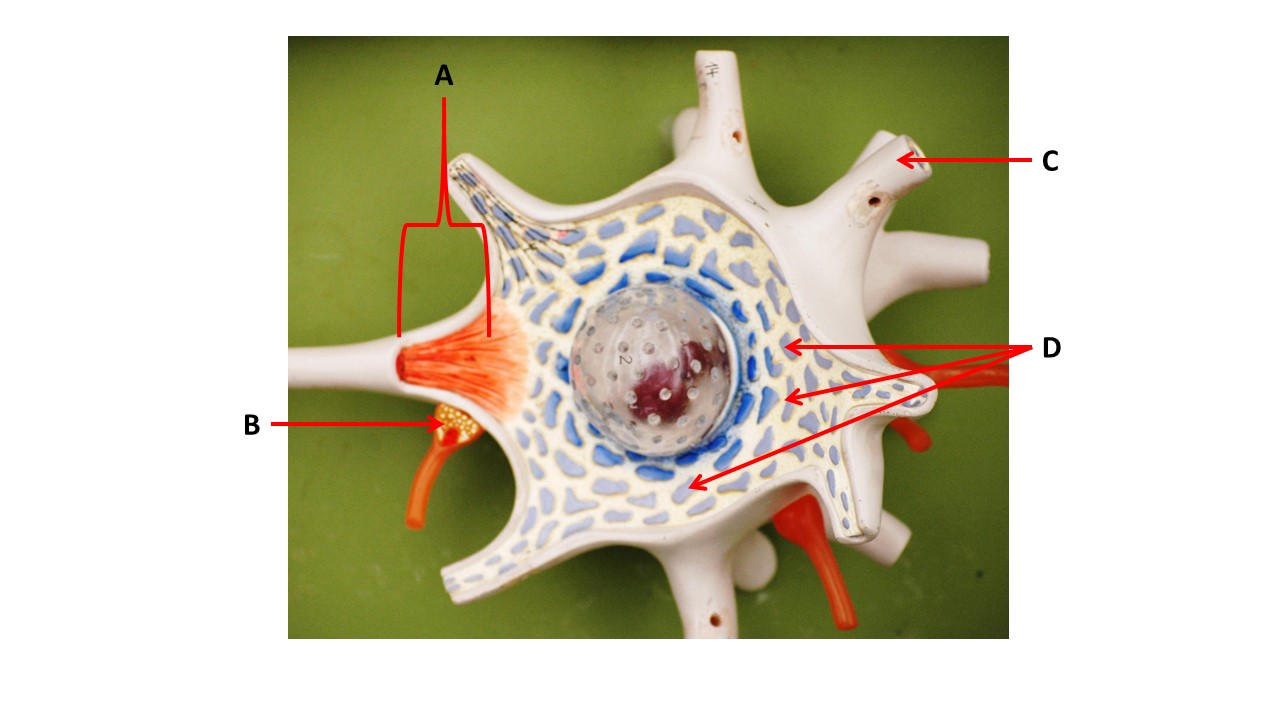

Name the region within bracket D.

medulla

Name the region of tissue surrounding the tip of arrow E.

lateral horn

The structures at the tips of arrows D are _____.

Nissl bodies

Name the region of tissue surrounding the tip of arrow B.

dorsal horn

Name the region of tissue surrounding the tip of arrow E.

lateral horn

Which structure(s ) would be found in the area at the tip of arrow D.

cell bodies of interneurons

Name the region of tissue surrounding the tip of arrow E.

ventral horn

Name the region within bracket G.

gray commisure